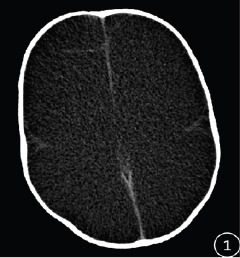

Results: At birth, the primitive reflexes were generally preserved in these infants, who exhibited a spectrum of symptoms including progressive enlargement of head circumference, epilepsy, cerebral palsy, intellectual disability, developmental delay, lethargy, convulsive spasms, and varying degrees of visual and auditory impairment. These infants may also present with other congenital malformations or abnormalities. The primary CT imaging findings revealed complete or near-complete absence of bilateral cerebral hemispheres, replaced by CSF. Specifically, there were 5 cases of complete absence of cerebral hemispheres, with minimal residual brain tissue observed in 17 cases. Bilateral ventricles were approximately normal in 3 cases and completely absent in 19 cases. Falx cerebri was incomplete or/and displaced in 12 cases, and 3 cases were concurrent with Dandy-Walker syndrome.

Conclusion: Hydranencephaly is a congenital disease characterized by destruction of the cerebral hemispheres. CT scan can provide accurate and reliable imaging evidence for the diagnosis of hydranencephaly.